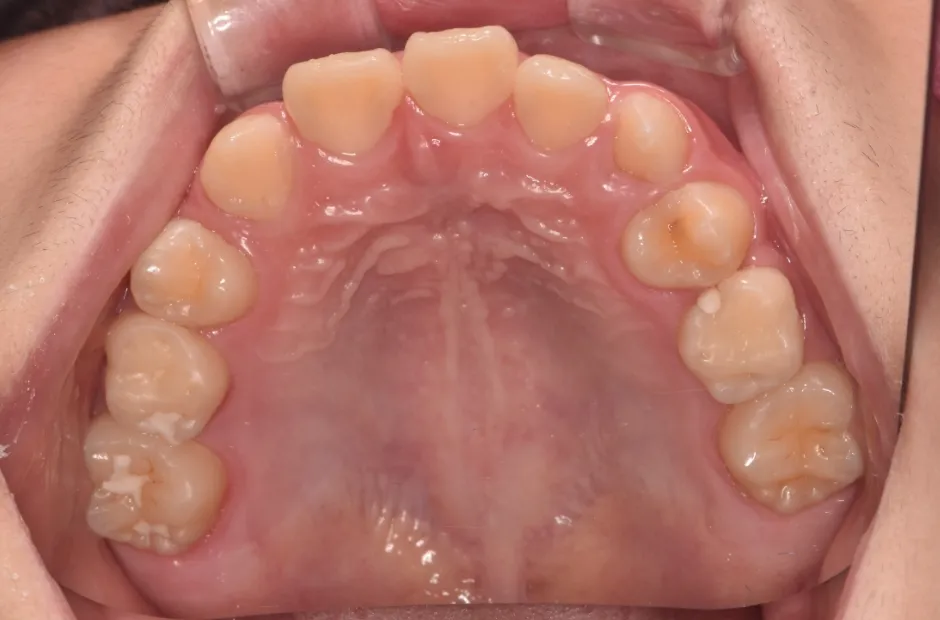

拡大床装置

叢生

| 診断名・主訴 | 叢生 |

|---|---|

| 年齢・性別 | 10歳・女性 |

| 治療期間・回数 | 2年半 |

| 治療に用いた主な装置 | 拡大床装置 |

| 抜歯部位 | なし |

| 治療費 | 30万円(税抜) |

| リスク・副作用 | 装置による違和感・疼痛・歯肉退縮・歯根吸収・虫歯のリスクなど |

治療前

治療中

治療後